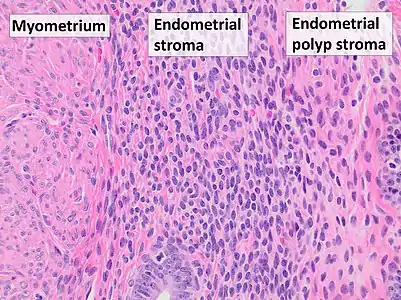

Pathology

Endometrial polyps can be solitary or occur with others.[12] They are round or oval and measure between a few millimeters and several centimeters in diameter.[7][12] They are usually the same red/brown color of the surrounding endometrium although large ones can appear to be a darker red.[7] The polyps consist of dense, fibrous tissue (stroma), blood vessels and glandlike spaces lined with endometrial epithelium.[7] If they are pedunculated, they are attached by a thin stalk (pedicle). If they are sessile, they are connected by a flat base to the uterine wall.[12] Pedunculated polyps are more common than sessile ones.[11]

Micrograph of an endometrial polyp. H&E stain

Micrograph of an endometrial polyp. H&E stain Myometrium (smooth muscle cells) versus endometrial stroma (more cellular) versus endometrial polyp stroma (more collagenous). H&E stain

Myometrium (smooth muscle cells) versus endometrial stroma (more cellular) versus endometrial polyp stroma (more collagenous). H&E stain